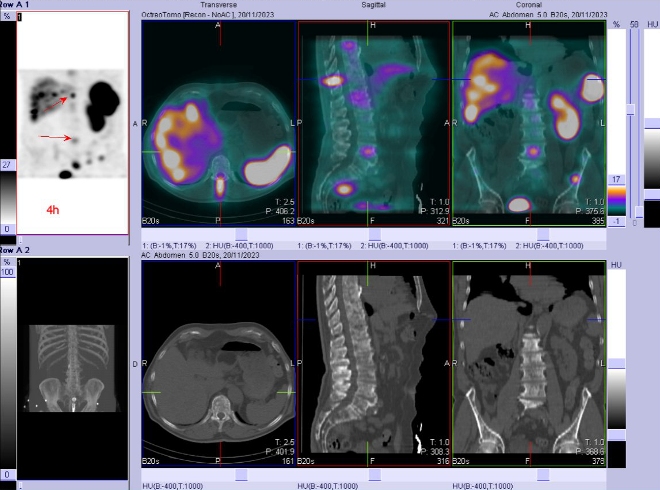

/ Obr. č. 2: SPECT/CT za 4 hod. po aplikaci OctreoScanu.

Popis: pozorujeme patologicky zvýšenou depozici radiofarmaka:

- v několika fokusech skeletu (nejkontrastněji v proc. spinosus Th10, dále v hrotu pyramidy os temporale vlevo, tělech Th3, Th6, Th8, Th12, L4, kosti kyčelní vlevo), vícečetně v žebrech oboustranně, v ldCT obraze mnohočetná smíšená převážně sklerotická ložiska

- nehomogenní kumulace v játrech, místy až s fokusy, nejnápadnější je v levém laloku ventromediálně

- v ložisku v malé pánvi pararektálně vlevo vel. cca 48x38mm

Akumulace v žlučníku, slezině, levé ledvině, močovém měchýři a střevních kličkách představuje fyziologickou distribuci.

Závěr: Mnohočetná ložiska patologicky zvýšené denzity somatostatinových receptorů, které odpovídají neuroendokrinní nádorové tkáni a generalizaci onemocnění (výrazně skelet, v ložisku v pánvi pararektálně a velmi suspektně v játrech).